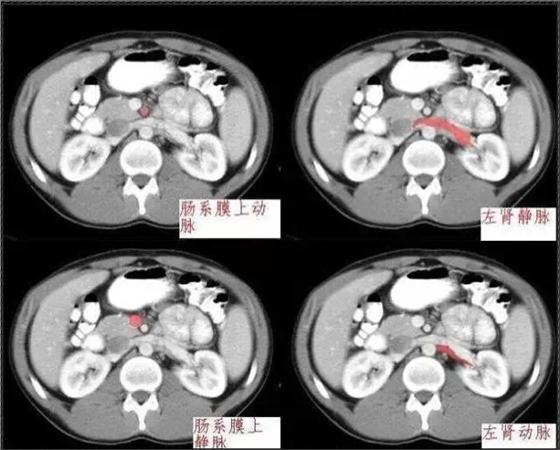

640.webp (7).jpg

640.webp (8).jpg

640.webp (9).jpg

640.webp (10).jpg